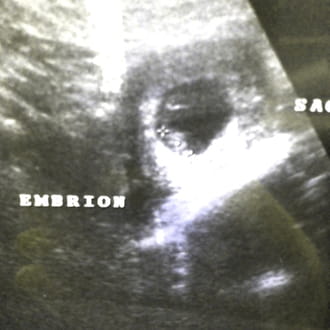

Ahora que te has enterado de estar embarazada, acude a que tu ginecólogo confirme la noticia. Esta es la manera como ellos calculan el embarazo:

Por medio de los controles prenatales podrá decirte la fecha exacta en la que ocurrió la concepción, cuando realice la ecografía del 1er trimestre, a las 12 semanas de amenorrea. Lee esto: